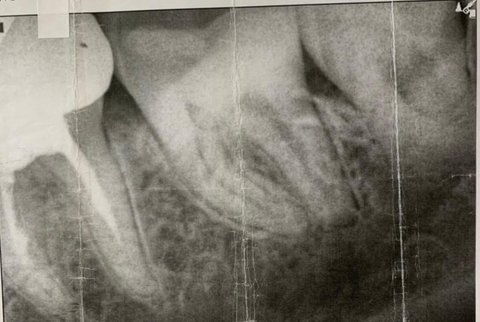

사랑니 뽑을때 찍은 사진 첨부합니다

파노라마는 돈이 많이 나와서 저렇게 찍었다고

의사 맘데로 결정하고 선택 했네요;;

이빨뿌리에 신경이 지나가는데;;저기엔 나오지도 않아요ㅠㅠㅠㅠㅠ

다른 치과에 가서 파노라마를 찍어보니 이빨 뺀 곳에 신경이 지나가는게 정확히 보이더라구요ㅠㅠ